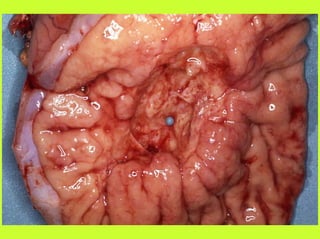

II - TRAITEMENT CHIRURGICAL

PRINCIPE I (REPARATION) : contrôle de la source

d’infection

PRINCIPE 2 (TOILETTE) : évacuer l’inoculation des

bactéries, le pus et par la toilette péritonéale et autres

méthodes

TRAITEMENT CHIRURGICAL (1)

PERITONITES

PRINCIPE 1 :

appendicectomie, omentectomie, suture d’une

perforation d’ulcère ou gastrique, exérèse d’un

cancer gastrique ou d’un cancer colique ou d’une

diverticulite perforée, pas d’anastomose en milieu

infecté

TRAITEMENT CHIRURGICAL (2)

PRINCIPE 2

Toilette péritonéale après prélèvement bactério,

aspiration du pus, pas d’évidence sur les

différentes séries de diminution de mortallité ou

des complications septiques postopératoires par

les lavages intra-abdominaux chez les patients

bénéficiant d’une antibiothérapie systémique, pas

d’avantage prouvé aux lavages avec antibiotiques

intra-péritonéaux (effets toxiques)